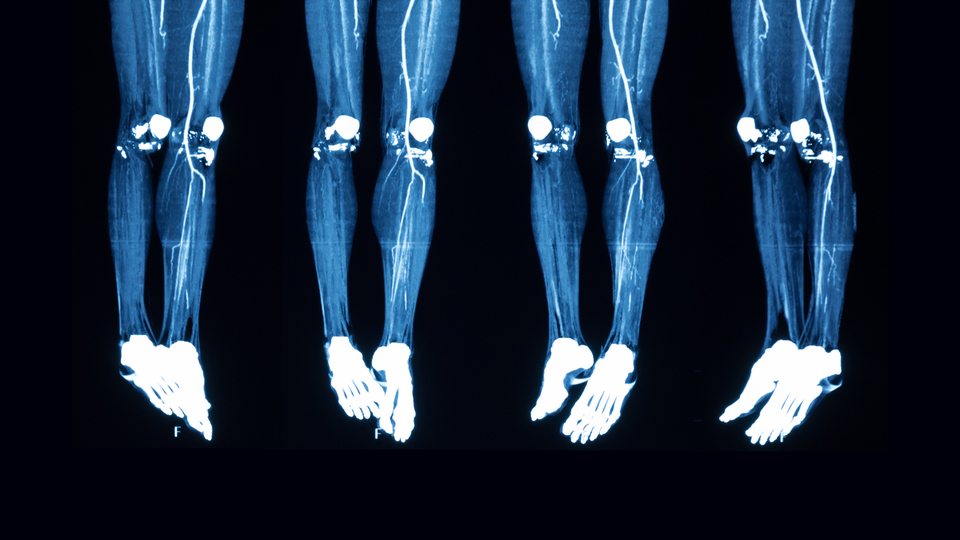

Yapılan bir çalışmaya göre, sigaranın sebep olduğu Buerger (budama) hastalığına bağlı uzuv kesilmeleri önlenebilir. Dünyanın en prestijli tıp dergilerinden olan "Journal of Invasive Cardiology"de yayınlarak tıp literatürüne giren çalışmanın detaylarını anlatan Sakarya Üniversitesi Tıp Fakültesi Kardiyoloji Anabilim Dalı öğretim üyesi ve Türk Kardiyoloji Derneği Yönetim Kurulu üyesi Prof. Dr. Ersan Tatlı, "Yayınladığımız çalışmamızda görüldüğü gibi, Buerger hastalığında yeni gelişen girişimsel teknikler ve damarlarda kan akış trafiğinin yeniden sağlanması stratejileri sayesinde ampütasyon oranları azalmaktadır" dedi.

2010 yılından beri Buerger hastalığı olup iyileşmeyen ayak yaraları olan hastalara transpedal adı verilen ayak topuğu ya da ayaküstü kılcal damarlardan girerek tıkalı damarları ters taraftan açtıklarını belirterek, "Normalde kasık bölgesinden girilerek dizaltı tıkalı damarlar açılabilmektedir. Ancak çoğu hastada kasıktan girilerek açılamayan ya da ayak üstünde yeterli damar yatağı olmadığı için ameliyata uygun olmayan hastalarda hibrit yöntem dediğimiz hem kasık hem de ayak üstü ve topuktaki kılcal damarlardan girerek damarları açıyoruz. Peki her damar açma işlemi yara iyileşmesini sağlar mı asıl önemli olan bu" dedi.

Prof. Dr. Tatlı, çalışmalarında hem bu yeni teknik uygulamanın (hibrit yaklaşım) amputasyonu (kol, bacak gibi organların tedavi amacıyla kısmen veya tamamen kesilip çıkartılması) engelleme üzerine etkilerini hem de yara iyileşmesini sağlamak için nasıl bir anjiyografik sonuç elde edildiği sorularının yanıtlarını araştırdıklarını söyledi.

Prof. Dr. Tatlı, sözlerine şöyle devam etti: "Bu yeni teknikle minör amputasyonların belirgin düzeyde azaldığını gösterdik. Yine yara iyileşmesinin olabilmesi için ayak tabanındaki damar yumağının (pedal loop) tamamen kanlanması gerektiğini gösterdik. Çalışmamızı dünyanın en prestijli girişimsel kardiyoloji dergilerinden biri olan "Journal of İnvasive Cardiology" dergisinde yayınladık. Çalışmamız hibrit yöntemle Buerger hastalığında şimdiye dek dünyada yapılmış en büyük vaka serisini içermektedir. Çalışma sonuçlarının bu hasta grubundaki tedavi yaklaşımlarını değiştirebileceğini düşünmekteyiz. Kliniğimizde 2016 yılından bu yana iyi organize olmuş yara bakım kliniği bulunmaktadır. Hastalarımızın tıkalı damarlarının açıldıktan sonra iyi bir yarabakım tedavisi almış olmaları da başarımızı sağlayan parametrelerden biridir."

Çalışmaya alınan hastaların çoğunun ümitsiz vakalar olduğuna işaret eden Prof. Dr. Tatlı, "Ayağında açık yarası olan, cerrahiye uygun olmayıp, daha önce kasıktan girilerek başarısız anjiyoplasti (anjiyo eşliğinde damar açma işlemi) olmuş olan vakalardı. Bu hasta grubunda yeni bir tedavi tekniğinin (hibrit tedavi) yaraları iyileştirerek amputasyonları azalttığını gösterdik. Yine bu çalışmada yara iyileşmesi için muhakkak ayak tabanındaki damar yumağına balon anjiyoplasti yapılarak kanlanmasının sağlanması gerektiği, aksi takdirde yaranın iyileşmeyeceğini ispatladık. Sadece sorumlu damarı açmakla yaranın iyileşmediği, hedefimizin pedal loop kanlanmasını sağlamak olması gerektiği, yeni teknik yaklaşımların çaresiz Buerger hastalarına yeni bir umut olabileceğini gösterdik" ifadelerini kullandı.